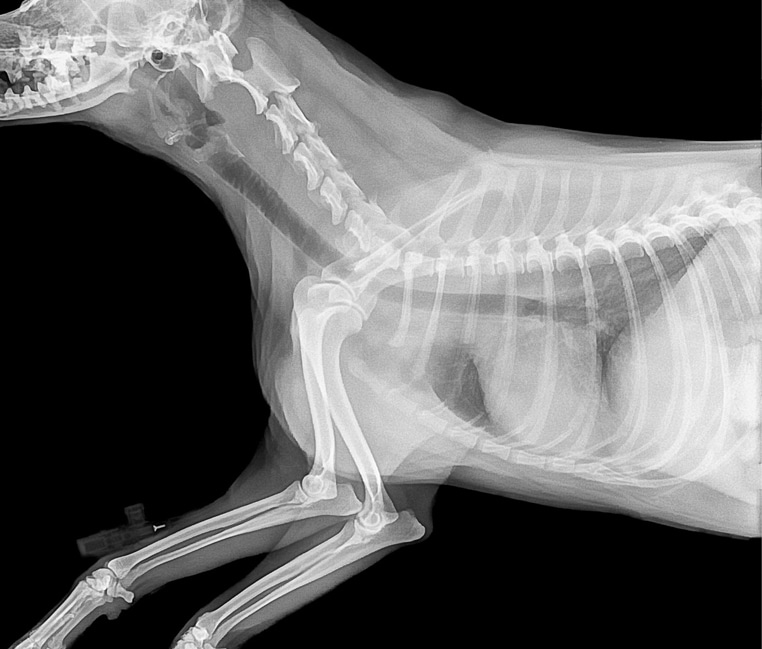

Un lien s’est tout de suite créé entre Margaret et Tide. Malheureusement, elle s’est rapidement rendu compte que quelque chose n’allait pas. En effet, un mois après l’adoption, Tide a eu des problèmes de transit et n’avait plus d’appétit. Ni une ni deux, Margaret l’a emmené chez le vétérinaire le plus proche, et malheureusement, la nouvelle est tombée… Tide souffrait de la maladie d’Addison.

Le vétérinaire a bien proposé un traitement pour soigner Tide mais malheureusement, bien trop onéreux pour la retraitée. Margaret, qui avait déjà dépensé toutes ses économies pour le soigner, ne pouvait donc pas financièrement, se lancer dans ce nouveau traitement. Heureusement, Victoria, sa fille, a eu la bonne idée d’ouvrir une cagnotte en ligne GoFundMe, en espérant récolter 2300 €. Mais Margaret et Victoria ne s’attendaient pas à un tel tournant !